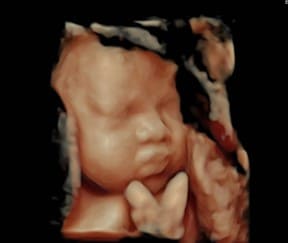

Sử dụng đầu dò 4D-5D để dựng lên hình ảnh 3 chiều của em bé, chuyển động theo thời gian thực là kĩ thuật siêu âm 4D-5D. Kĩ thuật này đòi hỏi bác sĩ có chuyên môn cao, khéo léo và cẩn thận, tỉ mỉ cũng như hệ thống máy móc hiện đại, để đánh giá chi tiết các cơ quan bộ phận của thai nhi. Những thời điểm được khuyến cáo nên đi siêu âm thai 4D-5D là

- Mốc thứ hai: khoảng từ tuần 21 đến tuần 24, lúc này thai đã gần hoàn thiện các cơ quan – bộ phận trong cơ thể như hệ thần kinh, hệ tim mạch, cơ quan vận động… Siêu âm thai còn dựng được hình ảnh mặt của em bé, đánh giá cấu trúc môi – mũi – tai, đánh giá tay chân của em bé xem có đủ ngón hay không, tay chân có khoèo không. Siêu âm thai còn đánh giá cấu trúc tim – đại động mạch, loại trừ các bệnh lý tim bẩm sinh. Đồng thời còn đánh giá các cấu trúc khác như bánh rau, dây rốn, nước ối…

Siêu âm thai 4D giúp quan sát mặt của em bé tốt hơn